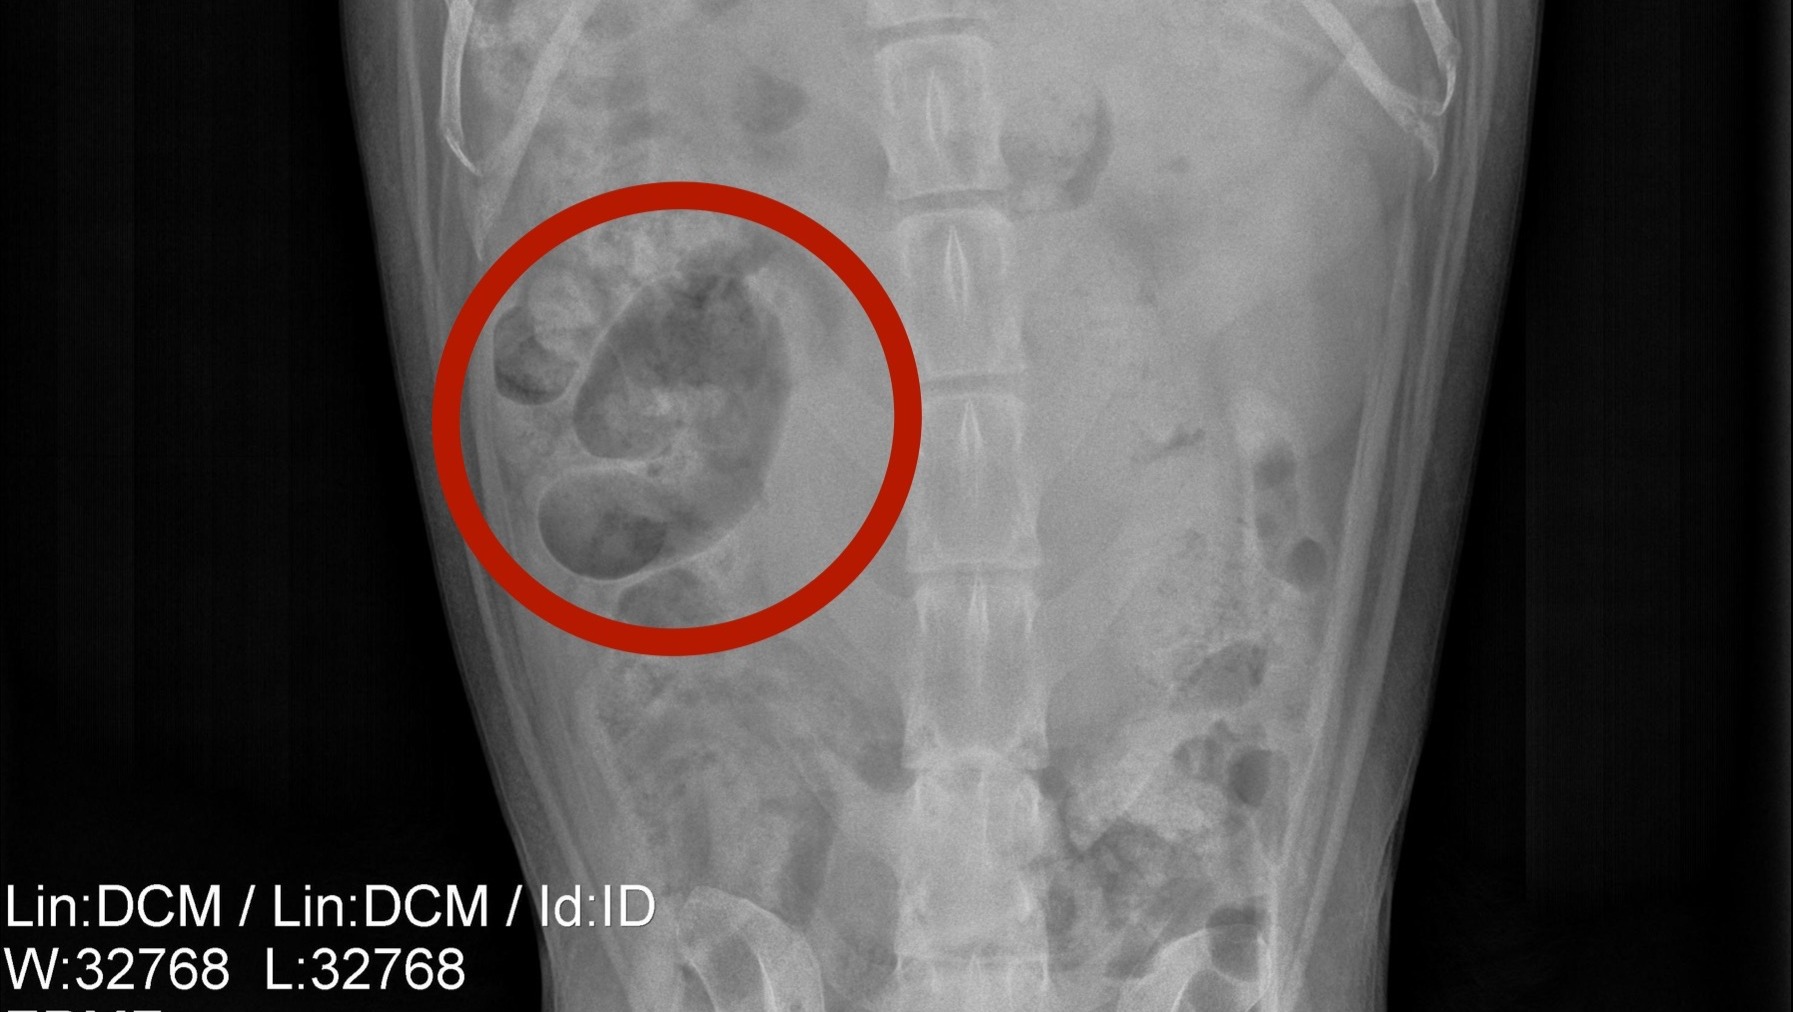

Unfortunately, we were given the news over the weekend that Bailey has been diagnosed with Splenic Hemangiosarcoma. It is known to be a very aggressive cancer that attacks the spleen, and unfortunately, long-term control / survival is difficult to achieve.

Bailey will undergo an emergency operation within the next 48 hours to remove the tumor before it ruptures and most importantly, slow the spread of cancer. Once removed, he will need to undergo further diagnostics to evaluate for any evidence of metastasis (spread of cancer to other areas of the body).